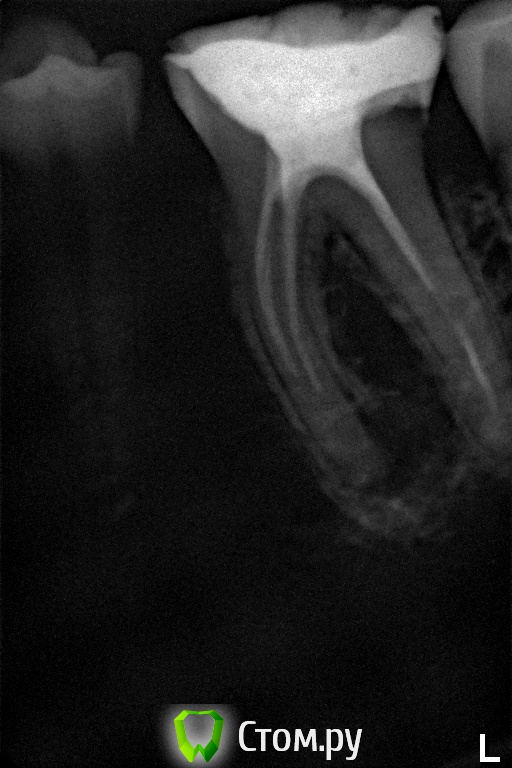

felicidade Опубликовано 23 июня, 2014 Поделиться Опубликовано 23 июня, 2014 (изменено) И снова добрый день Я хотела бы спросить, есть ли смысл в перелечивании каналов зуба №36 (девитализирован лет 10-12 назад), чтобы в будущем установить на корень литую культёвую вкладку и коронку? Каналы запломбированы жутко, под корнем есть киста, от самого зуба остались только стенки..Чисто физически, есть ли у него потенциал в плане дальнейшего протезирования, при условии, что перепломбировка каналов поможет, и киста чудесным образом уйдёт? Очень боюсь, что не выдержит жевательной нагрузки, что не на что попросту будет крепить протез.Врач-эндодонт в Любляне сначала подозревала резорбцию корня и оставленный в канале обломок иглы, но КТ показала, что ничего из этого нет. КТ я запросила у словенской клиники, в которой её делала, но пока на почту мне её не прислали, есть только такой снимок.Я, конечно, настроена на сохранение зуба, он меня никак не беспокоил все эти долгие годы (ТТТ), но хочу понять, стоит мне тратить 700 евро на эндо, или, может, лучше сразу удалять? Спасибо большое заранее p.s.Рентген сомнительного двадцать пятого зуба с неизвестным количеством корней/каналов смогу сделать и выложить только в середине июля в Любляне, т.к. тут в Италии рентген-снимки и КТ делаются строго по направлению врача. Изменено 23 июня, 2014 пользователем felicidade Ссылка на комментарий

DokDent Опубликовано 23 июня, 2014 Поделиться Опубликовано 23 июня, 2014 Вот ещё один снимок с Вашей панорамки. Теоретически можно перелечить и восстановить, но это 2-мерное изображение, поэтому по нему трудно судить об истинной картине что с корнями и вокруг них. Всё же лучше перед вмешательством посмотреть на кт. 1 Ссылка на комментарий